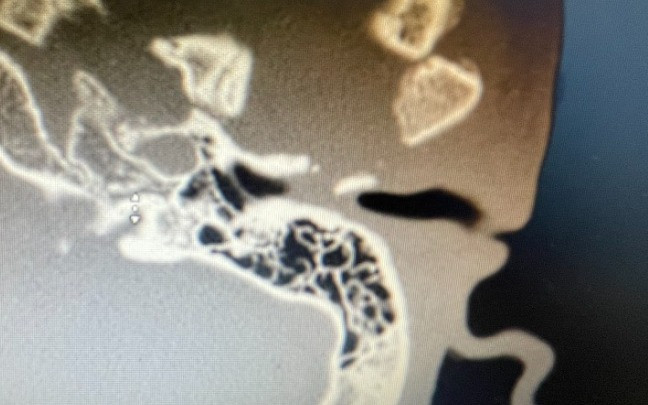

Sau khi nội soi tai mũi họng, các bác sĩ phát hiện ống tai ngoài bên trái của bệnh nhân bị chít hẹp hoàn toàn, chỉ còn một lỗ nhỏ kích thước lọt đầu tăm và đang viêm chảy mủ. Bệnh nhân có nghe kém dẫn truyền mức độ trung bình trên thính lực đồ. Chụp CT scan cho thấy hình ảnh tổ chức xơ chiếm 2/3 thể tích ống tai ngoài lan từ ổ vỡ cũ khớp thái dương hàm cùng bên (từ thành trước ống tai xương).

| Hình ảnh trước phẫu thuật |